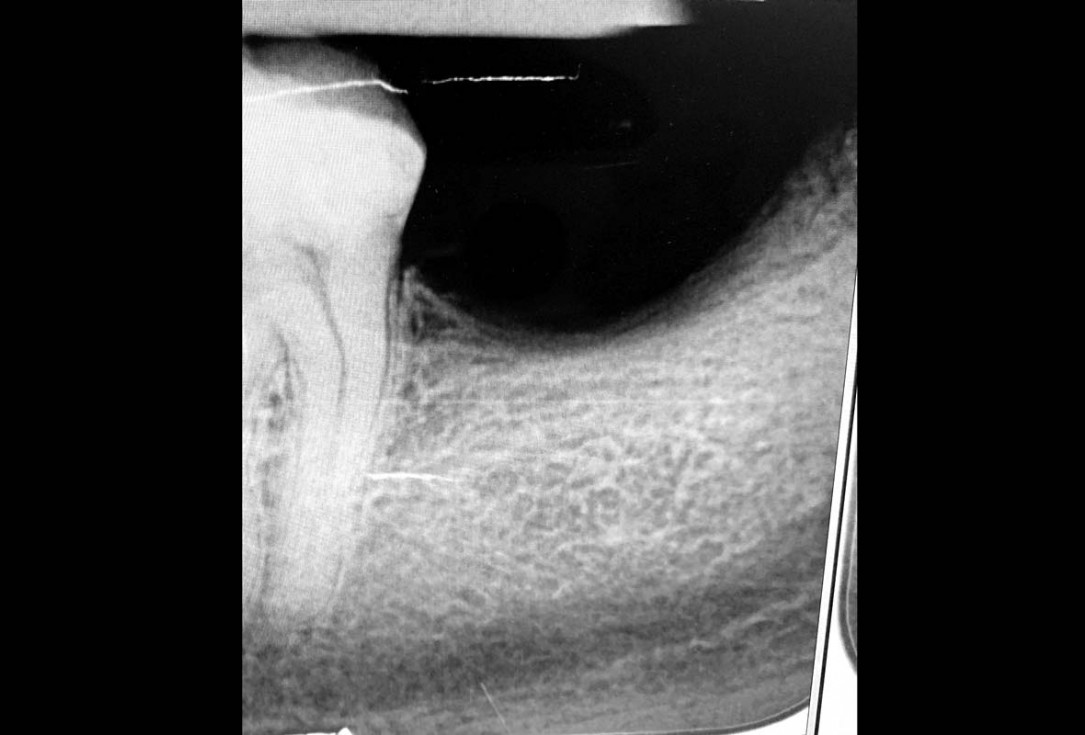

02/29 - Based on the intraoral x-ray a vertical bone defect of about 4 mm extending from 4.6 to 4.4 was determinedVertical bone augmentation and broadening of attached gingiva using cerabone®, permamem® and mucoderm® - Dr. R. Naimoli